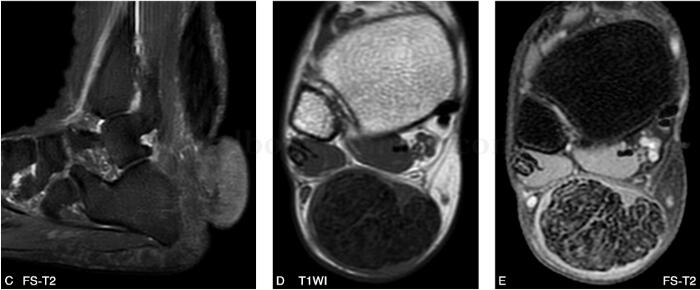

图1 MR:跟腱呈梭形增粗,各序列均以低信号为主,其间夹杂网格状稍高信号。跟腱后下方可见一不规则等低信号结节影,与肌肉信号接近,病灶自右下方包绕跟腱,并向外侧皮下突出

跟腱黄色瘤位于跟腱部位皮下,位置表浅,跟腱普遍增粗,呈梭形,有较为特征性的MR表现,但瘤体本身与跟腱多不能区分,一般情况下病变的信号变化多早于肌腱形态的改变,典型病变在T1WI像上呈跟腱长轴的类似肌肉的较低信号,在T2WI像上也呈较低信号影,其内有斑点状较高信号,在脂肪抑制上则表现的更加显著,病理上低信号为胶原纤维,高信号区域为含脂质的泡沫细胞及炎性反应。

本例于跟腱后下部跟骨附着点后方可见结节状软组织肿块,不完全性包绕肌腱生长,各序列近似于肌肉信号,术中及病理均证实该肿块与肌腱内病变组织成分相同,大体上均呈淡黄色,质软,由纤维组织及泡沫细胞构成,并可见胆固醇结晶。考虑系由于含胆固醇酯的巨噬细胞除在跟腱内灶状聚集外,同时在跟腱周围大量汇聚所致。